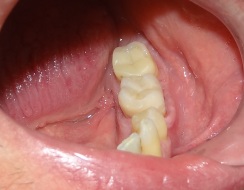

Odbudowa korony zęba trzonowego nakładem kompozytowym. Ząb przeleczono kanałowo i wzmocniono sztyftami z włókna szklanego.